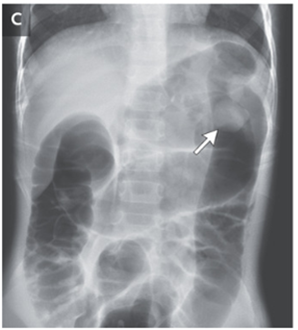

空気圧整復が行われ、腹痛は消失した。

処置後に腹部X線施行。矢印の部分にポリープと思われる塊が認められた。